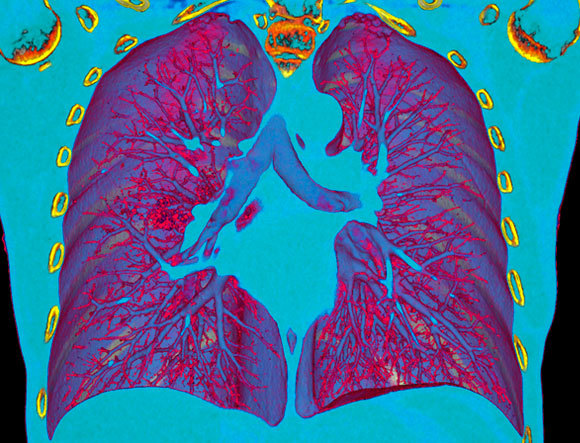

Tomography is an imaging method that allows division of the imaged object into 'slices'. Computerized tomography (or CT), usually involves a system that performs a series of two-dimensional X-ray images, obtained from different angles, which, when integrated by a computerized algorithm, provide a three-dimensional image of the documented organ.

CT is often used in medicine for the detection of internal bleeding, tumors, lung diseases, vein and artery problems, heart disease, gastrointestinal problems, and complex orthopedic problems such as joint fractures. This method provides high-resolution 3D images that facilitate an accurate diagnosis.

The main disadvantage of this imaging method is radiation damage. Since a CT scan consists of a series of X-rays, the patient is exposed to relatively high levels of ionizing radiation, which, as mentioned, can cause genetic mutations following high and prolonged exposure, and thus elevate the risk of cancer. The amount of radiation that the patient absorbs during such an examination depends on the size of the examined area, the number of photographs that make up the final image, known as a 'tomogram' , as well as the desired quality of the image. When a physician orders a CT scan, he or she must assess the risks and decide whether the benefit of obtaining a diagnosis, based on the imaging results, outweighs the risks of radiation exposure.

A CT scan enables the identification of pneumonia in a COVID-19 patient (the red spot left from the center of the image) | Source: VSEVOLOD ZVIRYK / SCIENCE PHOTO LIBRARY